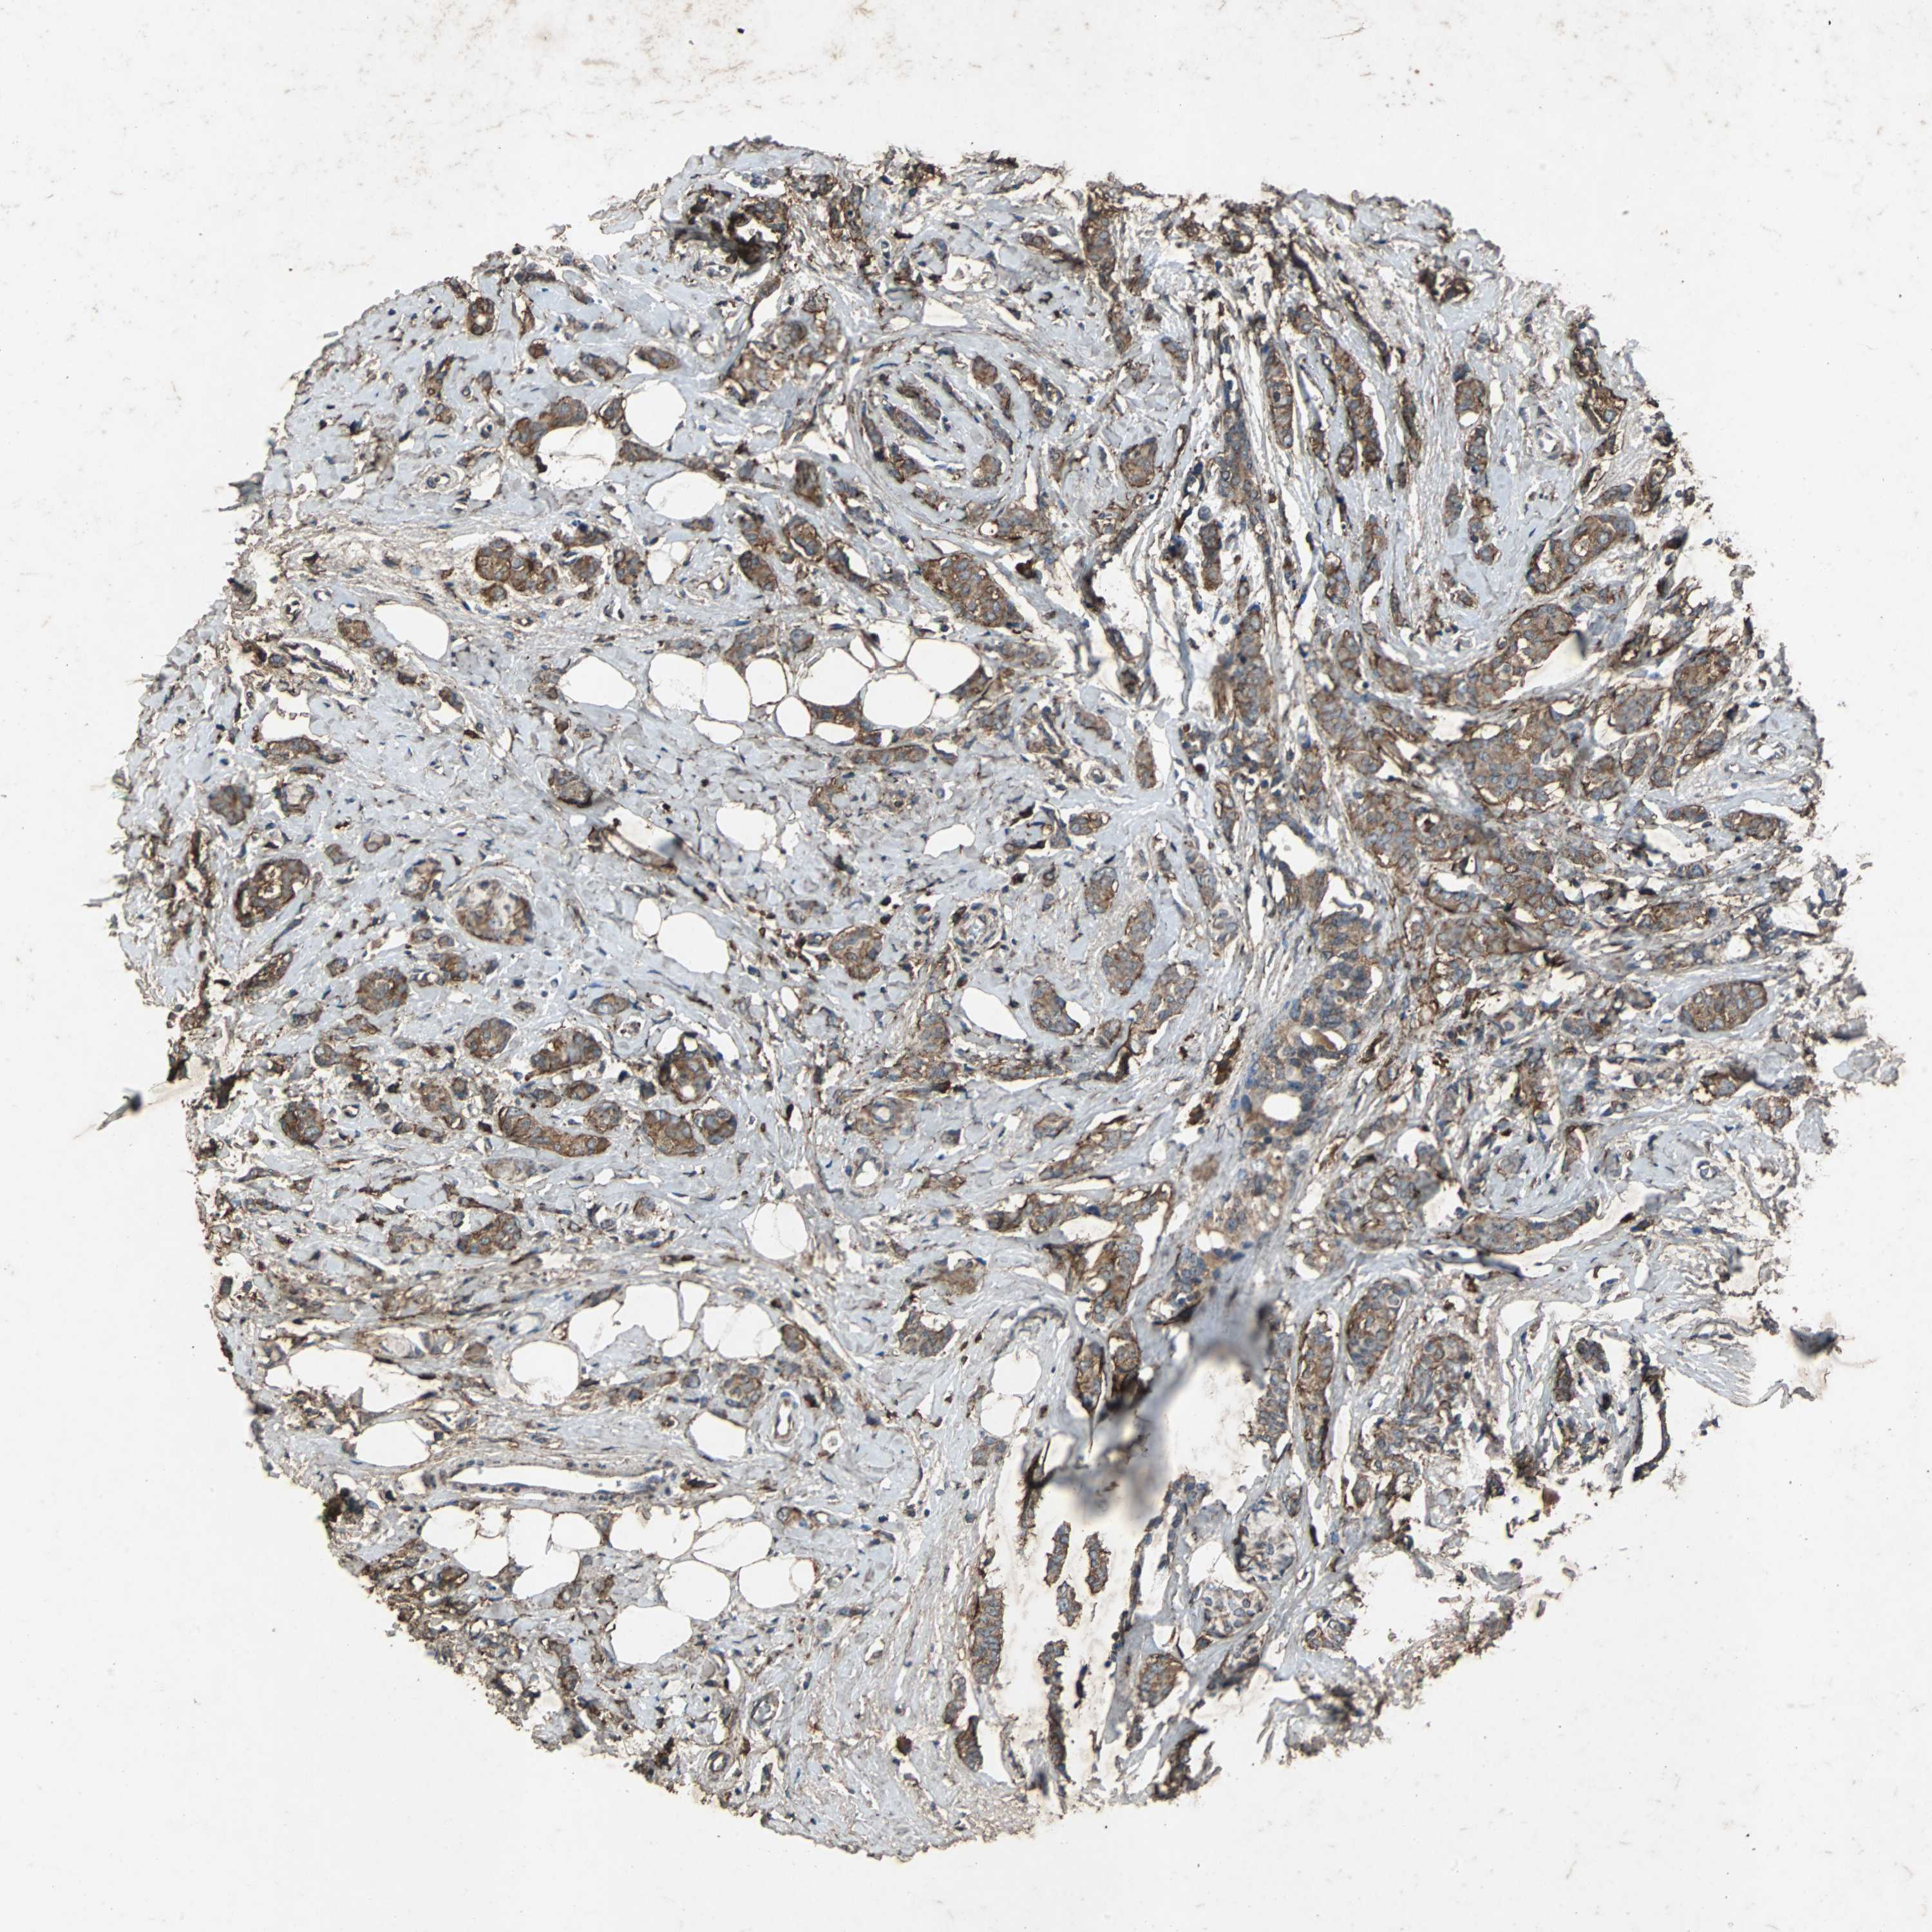

CANCER BREAST CANCER Show tissue menu

BRCA TCGA BRCA VALIDATION PROTEIN EXPRESSION

ANTIBODIES

AND

VALIDATION